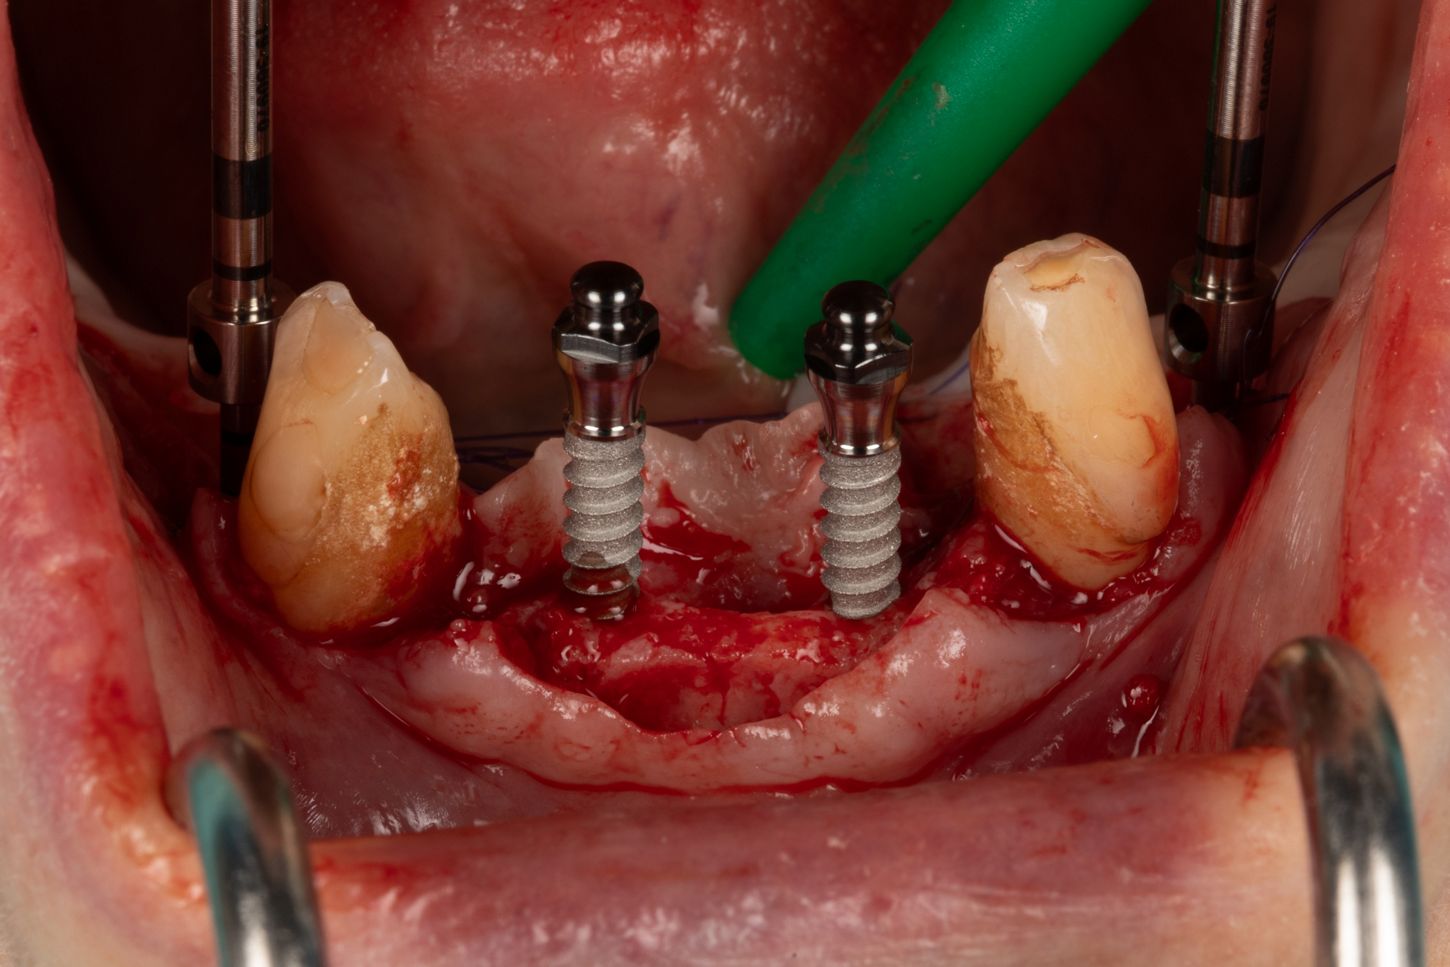

3a. Elevation of the full-thickness flap by crestal incision centred on the keratinised and sulcular tissues in 33 and 43.

The canines are preserved to provide an indication of the drilling axis.

Initial drilling in 32 and 42 using the first 1.5 mm drill bit, then positioning of directional indicators to assist with subsequent drilling. Drilling to 12 mm is checked using the graduation on the initial drill bit.

3a

3b

3b. Drilling adjacent to the remaining teeth 33 and 43 using the initial 1.5 mm drill. Depth and axis checked using the anterior indicators and residual canines.

Given the average bone density (D2 to D3), only the initial drill was used to the working length of 12 mm.

3c. Two mini-implants with a diameter of 2.6 mm and a length of 12 mm were placed in positions 32 and 42, first manually and then using a contra-angle. The insertion torque recorded at the end of the procedure was 21 N.cm in 32 and 17 N.cm in 42. The implants were positioned 0.5 mm subcrestal, i.e. with slight burial of the smooth neck.

3c

3d

3d. Two mini-implants with a diameter of 2.6 mm and a length of 12 mm were placed in positions 34 and 44 using the same protocol as for the previous mini-implants. The torque obtained was 27 Ncm in 34 and 37 Ncm in 44.